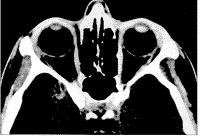

我们对病人初次检查时,其双眼最佳矫正视力20/20,左眼外眦部轻度肿胀,在外眦周围皮肤上有少量干燥的结痂(图1)。眼外运动充分,容易将双眼推回眶内。没有突眼。触诊显示外眦部有一小的、无触痛性肿块。活组织显微镜检查显示左眼结膜中度充血。有白色脓性物质通过外眦部结膜一个针尖大小的区域排出(图2)。右眼活组织显微镜检查和双眼检眼镜检查均正常。眼眶的计算机X线断层照相术扫描显示无异常(图3)。

图3 眼眶计算机X线断层照相扫描无异常